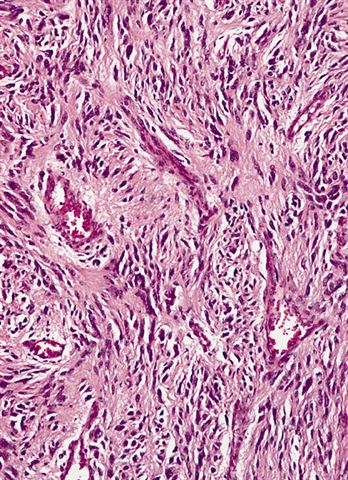

Microscopic (histologic) description

- High grade dedifferentiated liposarcoma

- Dedifferentiated component is a cellular and typically a nonlipogenic sarcoma with significant pleomorphism

- Often resembles malignant fibrous histiocytoma (MFH), now referred to as undifferentiated pleomorphic sarcoma (UPS), with short fascicles of pleomorphic spindle cells associated with mixed inflammatory infiltrate

- Can show a peculiar whirling pattern reminiscent of meningothelial structures (Histopathology 1998;33:414, Am J Surg Pathol 1998;22:945)

- Low grade dedifferentiated liposarcoma

- Less common low grade tumor resembling fibromatosis or well differentiated fibrosarcoma

- Nonlipogenic (in contrast to well differentiated spindle cell liposarcoma, which contains atypical fat / lipoblasts)

- Considered by some to be the same as cellular atypical lipomatous tumor, although there is evidence that even low grade dedifferentiation is associated with a poorer prognosis when compared with conventional atypical lipomatous tumor

Microscopic (histologic) images

Contributed by Michael R. Clay, M.D. and AFIP